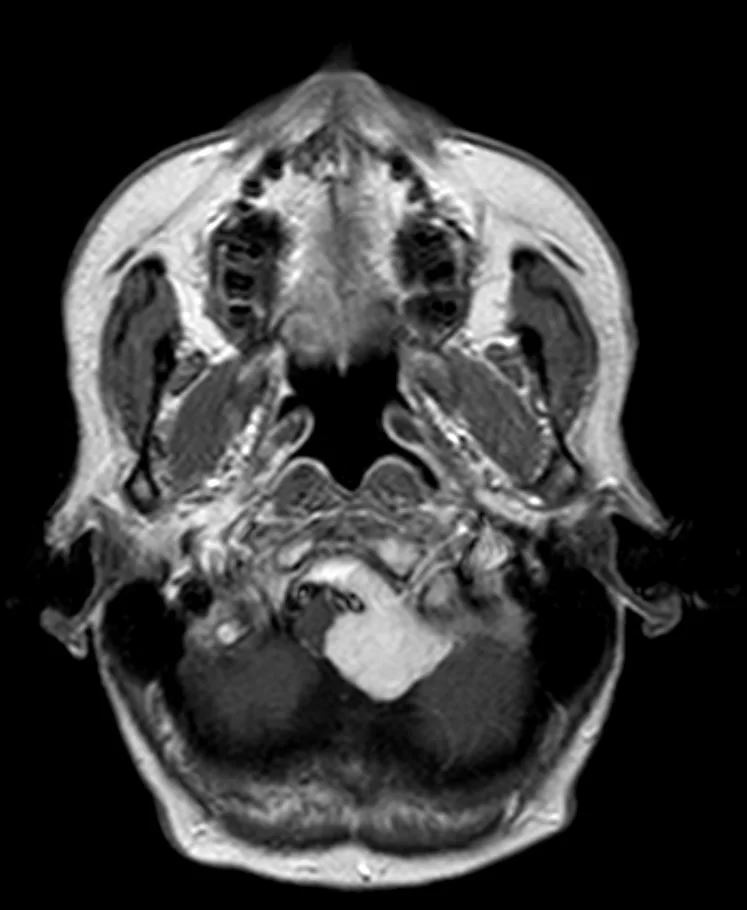

Επιδερμοειδής όγκος δεξιάς γεφυροπαρεγκεφαλιδικής γωνίας

Ασθενής 19 ετών με γνωστή χωροκατακτητική εξεργασία (επιδερμοειδες γεφυροπαρεγκεφαλιδικής γωνίας δεξιά) με προοδευτικά σημαντική αύξηση μεγέθους. Νευρολογικά ακέραιος. Ο απεικονιστικός έλεγχος με μαγνητική τομογραφία ανέδειξε

Περισσότερα